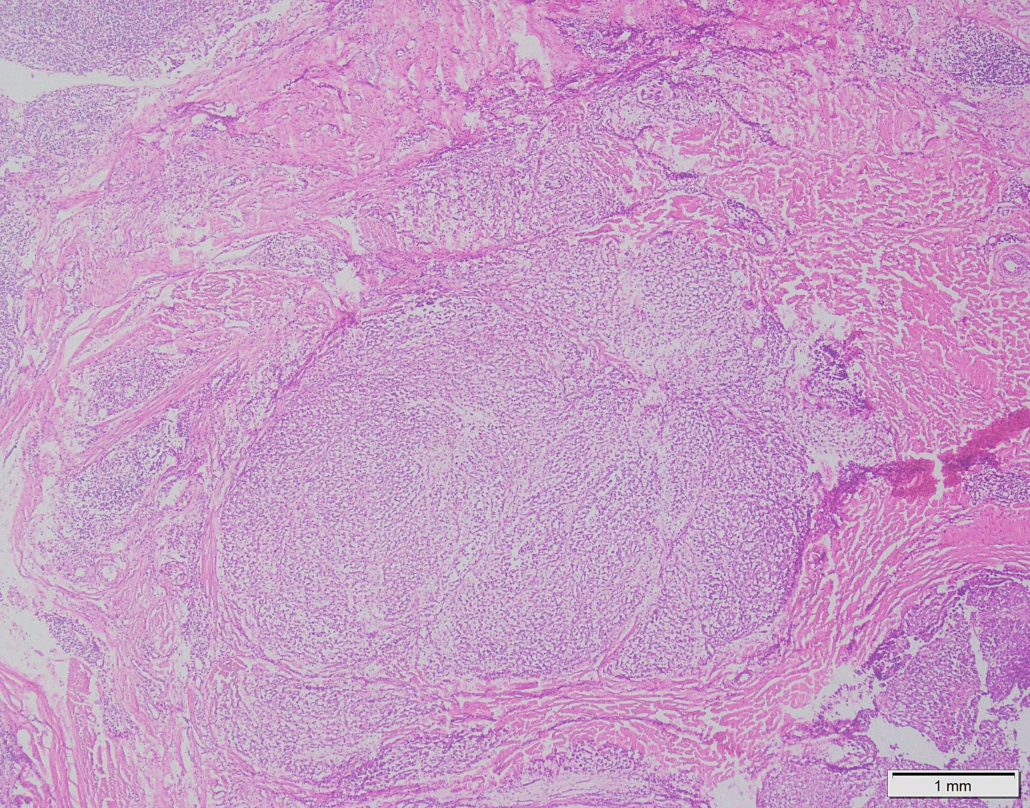

Case 03

Case presented by Dr Shaarif Bashir, FCPS (PAK), Shaukat Khanum Memorial Cancer Hospital and Reserach Centre, Pakistan